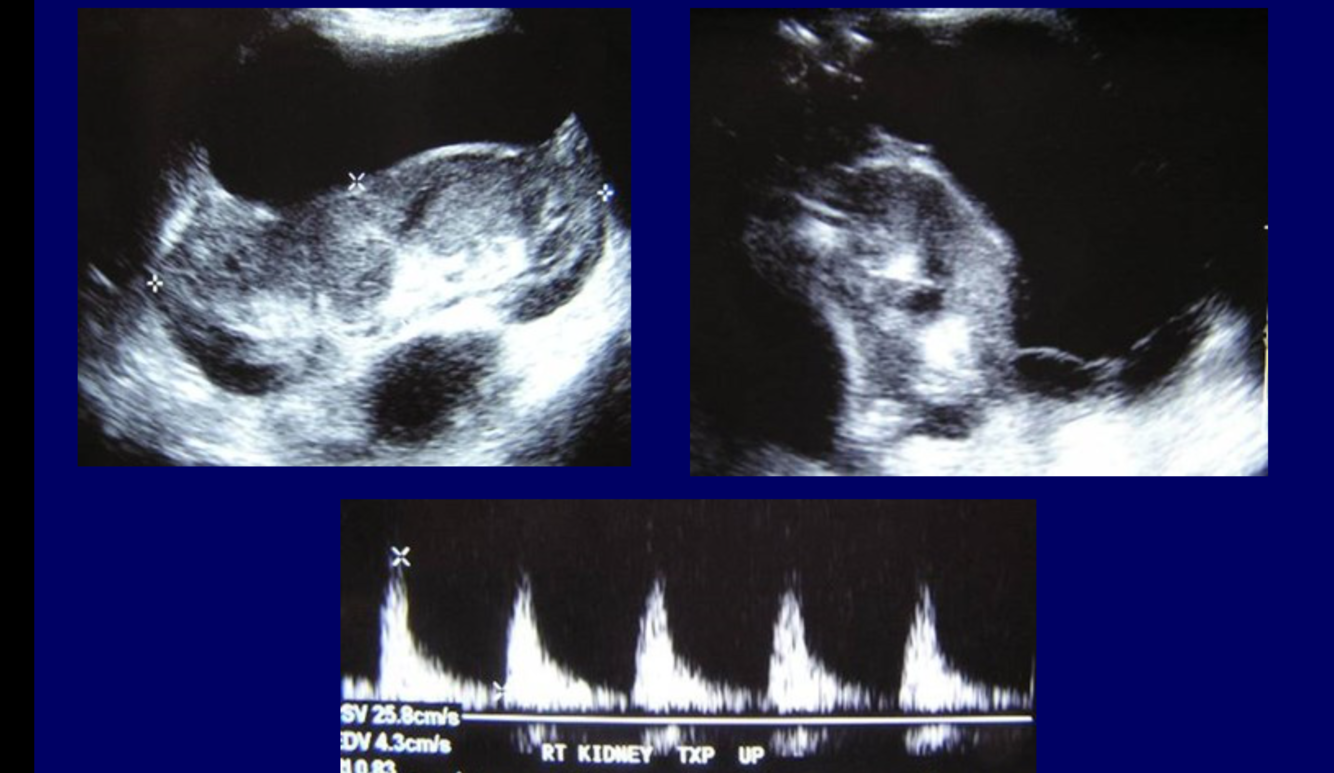

Ultrasound

Ultrasound is usually performed in this setting to assess the renal parenchyma and exclude other causes of obstruction. In acute tubular necrosis, the kidneys usually have a normal appearance on ultrasound, but may be enlarged and increased echogenicity 5.

What are the signs of renal vein thrombosis in the kidneys on USS?

Early and late phases

Kidneys